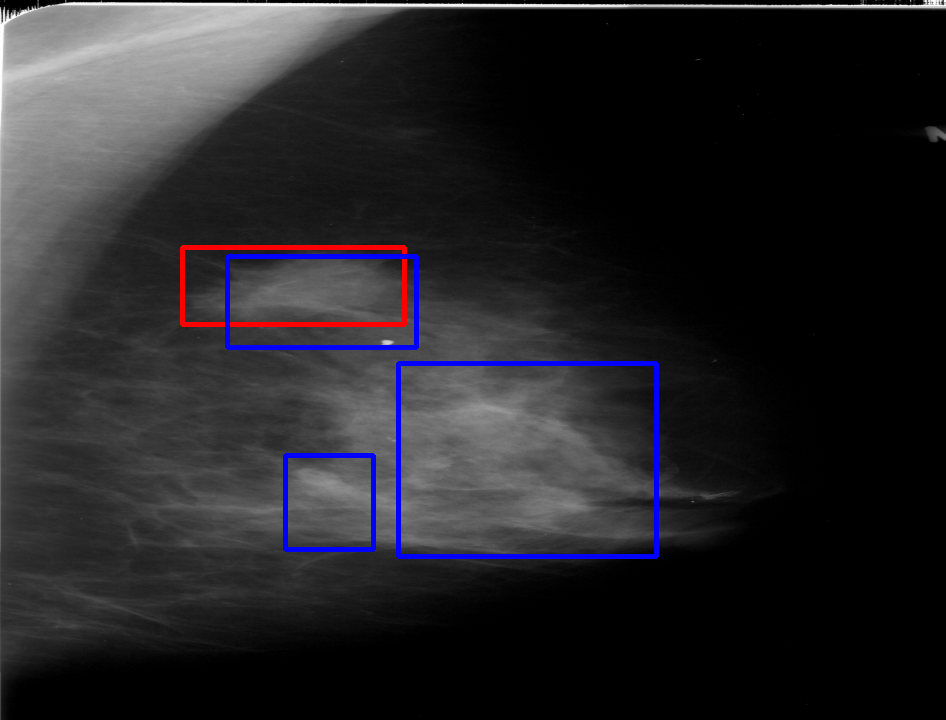

UDA has been extensively studied in case of natural images, utilizing techniques such as adversarial learning [21],pseudo-label training [6, 21, 40], image-to-image translation [40], graph reasoning [20], and adaptive mean Teacher training [6], improving domain adaptation efficiency of object detectors. Recently multiple works focused on using Mask autoencoders (MAE) methods in large-scale pretraining for vision models, involving masking parts of input and reconstructing them [12, 33]. However, these approaches overlook domain shifts. Alternatively, widespread utilization of Teacher-Student models, wherein a Teacher provides pseudo-labels for target domain (unlabeled images) to supervise a Student model, leads to notable adaptation improvements [40, 43]. However, these techniques face the challenge of incorrect predictions and excessive false positives per image due to low-quality pseudo-labels, particularly for medical imaging problems. Pseudo-labels are filtered from the Teacher model’s outputs based on the confidence score threshold. Selecting numerous pseudo-labels with low thresholds leads to inclusion of incorrect predictions, and compromising performance. Conversely, higher thresholds yield a limited number of pseudo-boxes, resulting in sub-optimal supervision. Existing Teacher-Student models often produce pseudo-labels riddled with errors and false positives, as illustrated in Fig. 1(a) and Fig. 1(b). Though [21, 40, 43] utilize techniques like adversarial alignment, weak-strong augmentation, and selective retraining of Student model to minimize the false positives in pseudo-labels, these approaches fail on medical images.

Contributions of this work. We note that screening mammography inherently differs from natural images, with breast abnormalities such as masses, asymmetries, and micro-calcifications, typically much smaller in comparison to the salient objects present in natural images, emphasizing the need for approaches specific to this problem. To address these issues, we make following contributions in this work: (1) We introduce D-MASTER, a transformer-based Domain-invariant Mask Annealed Student Teacher Autoencoder Framework for cross-domain breast cancer detection from mammograms (BCDM), integrating a novel mask-annealing technique and adaptive confidence refinement module. Unlike pretraining with mask autoencoders (MAEs) [12], leveraging massive datasets for training and then fine-tuning on smaller datasets, we present a novel learnable masking technique for the MAE branch that generates masks of different complexities, which are reconstructed by the DefDETR [44] encoder and decoder. Our approach, as a self-supervised task on target images, enables the encoder to acquire domain-invariant features and learn better target representations as shown in Fig. 1(c). (2) In Teacher-Student model, since the pseudo-label noise generated by the Teacher affects the Student model severely, we propose an adaptive confidence refinement module that progressively restricts the confidence metric for pseudo-label filtering. During the initial adaptation phase, soft confidence is applied allowing more pseudo-labels to learn better target representations. Subsequently, as confidence gradually increases, the focus shifts towards enhancing detection accuracy by prioritizing more reliable pseudo-labels. (3) We release a bounding box annotated subset of 1000 mammograms from the RSNA Breast Screening Dataset (referred to as RSNA-BSD1K) to support further research in BCDM. (4) We setup a new state-of-the-art (SOTA) in detection accuracy for UDA settings. We report a sensitivity of 0.74 on INBreast [25] and 0.51 on DDSM [18] at 0.3 FPI, compared to 0.61 and 0.44 using current SOTA respectively. Significant performance gains are also observed on our in-house and RSNA-BSD1K datasets.